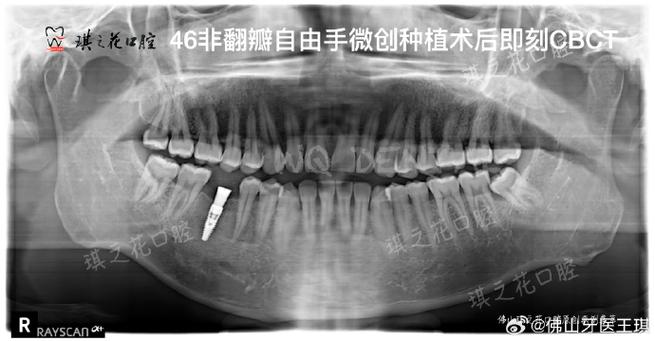

种牙CT测量数据是连接影像诊断与外科操作的桥梁,医生需通过多平面重建(MPR)、曲面体层(Panoramic)及三维(3D)视图综合分析,结合数字化导板技术,实现种植体的精准定位,最终达到功能与美学的统一,随着人工智能辅助诊断的发展,CT数据的自动化测量与分析将进一步提升手术效率与安全性,为种植牙技术提供更可靠的保障。